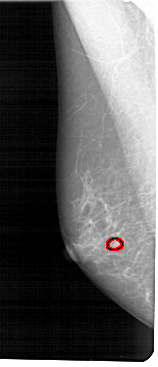

A_1545_1.RIGHT_CC

RIGHT_CC LINES 5131 PIXELS_PER_LINE 2266 BITS_PER_PIXEL 12 RESOLUTION 43.5 NON_OVERLAY

FILE: A_1545_1.LEFT_CC.OVERLAY

TOTAL_ABNORMALITIES 1

ABNORMALITY 1

LESION_TYPE MASS SHAPE LOBULATED MARGINS OBSCURED

ASSESSMENT 4

SUBTLETY 2

PATHOLOGY BENIGN

TOTAL_OUTLINES 1